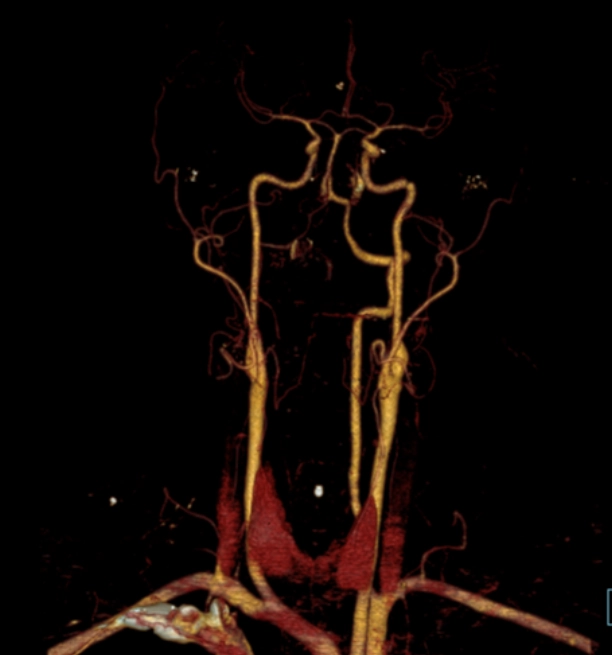

Tổn thương mạch máu não-cổ do chấn thương kín (Blunt Cerebrovascular Injury - BCVI)

Thang điểm Biffl phân loại tổn thương mạch máu não do chấn thương cùn (Blunt Cerebrovascular Injury - BCVI)